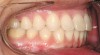

Figure 7a  This case is an example of the importance of evaluating the bite with the joints seated in a stable position. Orthodontic treatment was rendered to correct a "deep overbite" and trauma to the maxillary incisors. A) Handheld models in maximum intercuspation at beginning of treatment. The deep overbite is apparent.

Figure 7a

Figure 7b  This case is an example of the importance of evaluating the bite with the joints seated in a stable position. Orthodontic treatment was rendered to correct a "deep overbite" and trauma to the maxillary incisors. B) Handheld models showing correction of the deep overbite after orthodontics has been completed. The patient complained of "jaw" discomfort after orthodontic treatment.

Figure 7b

Figure 7c  This case is an example of the importance of evaluating the bite with the joints seated in a stable position. Orthodontic treatment was rendered to correct a "deep overbite" and trauma to the maxillary incisors. C) Models mounted in CR after use of a superior repositioning splint to stabilize the joints. With stabilized joints, the true malocclusion is uncovered. The patient went back into orthodontic treatment and required mandibular advancement surgery.

Figure 7c

Figure 7d  Intraoral view of the occlusion of patient from Figure 7 after retreatment. The occlusion is adequate to finish with equilibration. D) Models mounted in CR after retreatment.

Figure 7d